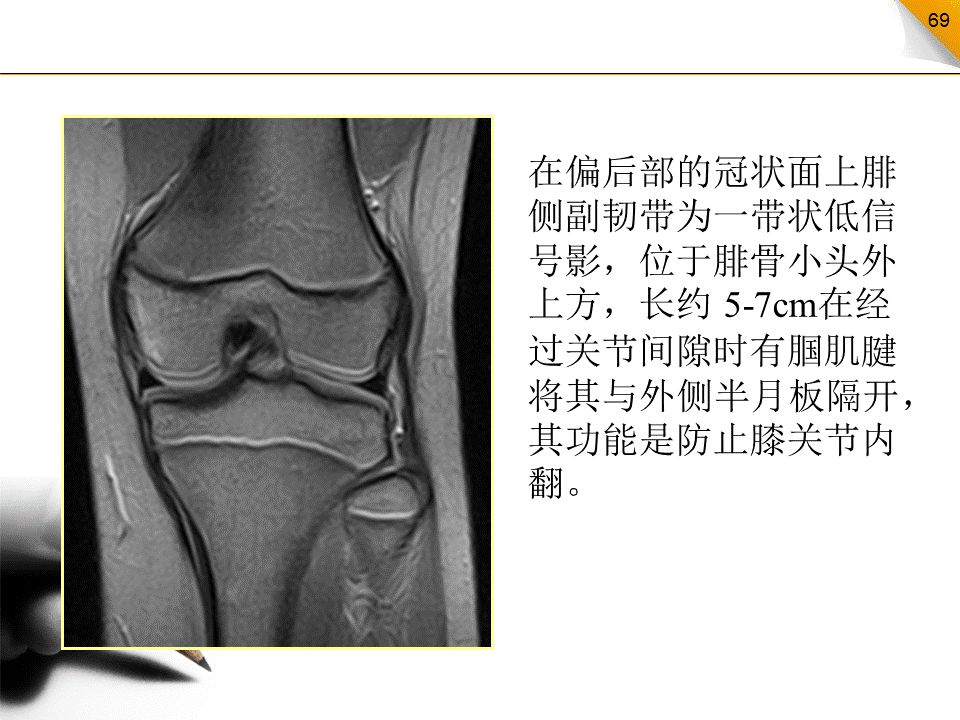

膝关节韧带

包括前交叉韧带、后交叉韧带、内侧副韧带、外侧副韧带、囊韧带、板股韧带、髌支持带、横韧带等

最易损伤的是前交叉韧带和内侧副韧带